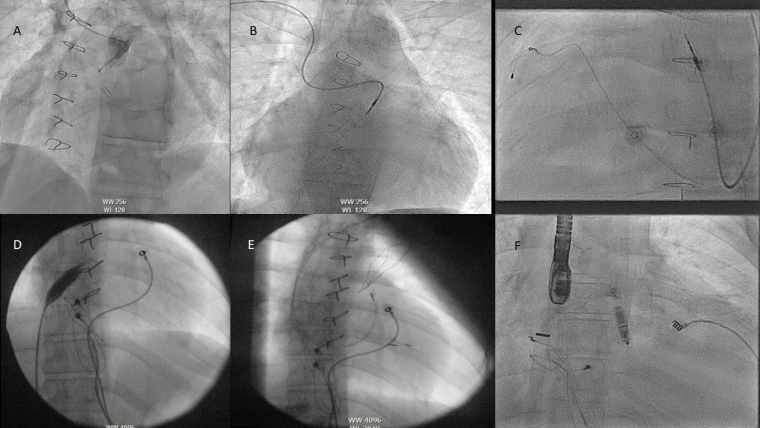

As leadless pacing becomes more popular, operators will need to be more aware of complex lower limb abnormalities that may occur precluding easy inferior venous access to the heart, such as an interrupted inferior vena cava (IVC) in atrial isomerism [6]. In these cases, a superior approach from the appropriate jugular may be used.

In addition to vascular abnormalities, a childhood history of multiple interventions often leads to vascular occlusion and stenoses making access difficult and techniques utilising micropuncture or recanalisation may be needed.

Next in periprocedural preparation is to plan how to deliver the lead or leadless device which may require an understanding of obstructions such as baffles, conduits and valve replacements which are more relevant as the complexity of CHD rises. In addition to just delivering a lead to a location there can be issues as to whether the area the cardiologist can reach is paceable, such as in the Fontan circulation [7].

In CHD the incidence of coronary sinus abnormalities is much higher with abnormalities such as a persistent left SVC, an unroofed coronary sinus or an absent coronary sinus (CS) making traditional lead delivery difficult or impossible [12]. In these cases, sometimes Thebesian veins or collateral veins can be utilised. In some pathologies the CS may not be accessible at all for resynchronisation, such as the atrial switch for D-TGA.

Whilst not complex defects on their own, these can cause issues for the implant team due to the difficulty of making sure that one has not crossed into the left atrium or left ventricle inadvertently, via the defect. In these cases, careful tracking of the atrial lead into the IVC before retracting back/deployment with multiple views is helpful, as is advancing the ventricular lead into the pulmonary artery/ventricular outflow tract to confirm positioning. In addition to this, direct pressure measurement or angiography can be used to support lead positioning or a leadless device.